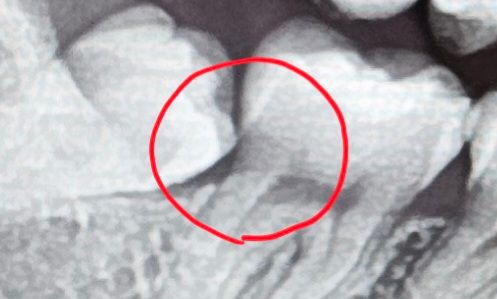

사진속 어금니에 충치가 있는지 궁금합니다

치아 사진중 어금니와 사랑니 사이에 탁한색의 홈? 같은게 보이는데 혹시 이게 충치인지 여쭤보고싶습니다..!

맞다면 바로 치료가 필요한 상태인지 궁금합니다.

방사선 사진으로는 음영으로 보이고 있기때문에 충치가 있을 가능성이 높습니다.

하지만 정확한 확인을 위해서는 해당부위를 육안으로 확인을 해야 합니다.

충치 가능성이 있어보입니다. 해당 부분은 중첩이 일어나기 쉬운 부위라 다른 여러 검사 방법을 통해 종합적인 진단이 필요합니다,

저부분은 엑스레이의 오류일 가능성이 잇어서 사랑니를 발치하고 나서 확인을 다시 해봐야 될것같습니다.

옆의 부분매복사랑니로 인해 생긴 충치일 가능성이 있습니다 사랑니 발치하면서 확인이 가능할 것 같습니다